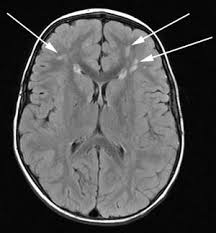

eg there is evidence of the stroke on mri

its probably vascular caused memory issues